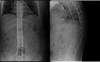

- osteopenia

scoliosis

* PE

* neuro exam for reflexes, motor, sensory function

* gain analysis

* tests

* full-length PA and lateral films

* EMG (radiculopathy vs. neuropathy)

* Tx

* skeletally immature

* observation, bracing (25-45 deg), fusion (\>45 deg)

* Milwaukee or Boston brace

* mature

* conservative tx, surgical if curve \>50-60 deg

122